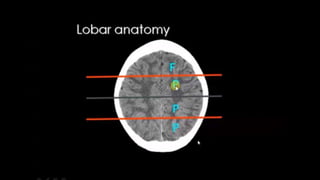

LOBES

TEMPORAL LOBE CONTOURING Francis Ho, MEDICEINE,2018